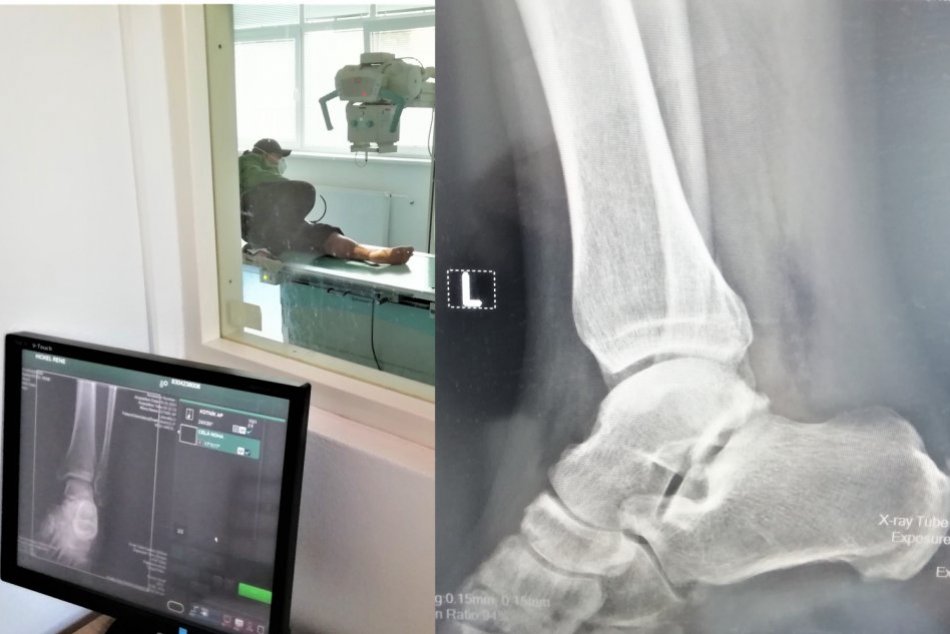

Oddelenie patrí bez ohľadu na aktuálnu pandemickú situáciu medzi najvyťaženejšie v nemocnici. „K najčastejším výkonom patria vyšetrenia pľúc a skeletu,“ potvrdila poverená riaditeľka nemocnice Nina Horniaková.

Röntgenológia v Zlatých Moravciach

Zdroj: AGEL SK